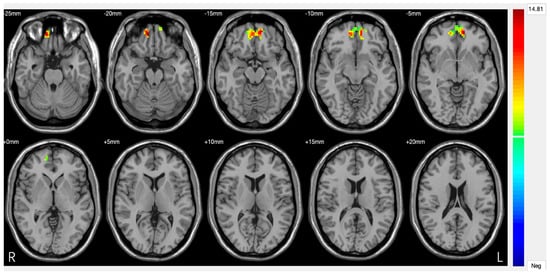

Amygdala. The amygdala serves as a crucial neural hub in depressive pathophysiology, representing the primary centre for negative emotion processing and threat response coordination [62]. Functional alterations of this structure result in pathological amplification of negative emotional responses while compromising fear extinction mechanisms, significantly contributing to the emotional dysregulation characteristic of DS. Neuroimaging studies consistently document amygdala hyperactivation patterns in response to negative emotional stimuli, with BOLD activity increases of 40–60% compared to healthy controls [63]. This hyperresponsivity shows selective characteristics, being particularly pronounced for negatively valenced stimuli while paradoxically reduced for positive stimuli, suggesting specific dysregulation of emotional processing circuits rather than generalized emotional reactivity (Figure 3). The basolateral amygdala demonstrates specific alterations in synaptic plasticity, with reduced GABAergic inhibition effectiveness leading to increased neuronal excitability [64]. High-resolution magnetic resonance studies have revealed microstructural modifications, including 12–18% increases in cellular density that correlate with symptom severity [65]. Connectivity between the amygdala and VMPFC shows significant compromise in DS, with 30–45% reductions in functional synchronization during emotional regulation tasks [66]. This disconnection compromises prefrontal top-down modulation effectiveness, perpetuating amygdala hyperactivation and limiting cognitive emotional control capacity. Diffusion tensor imaging studies have identified corresponding white matter alterations in tracts connecting the amygdala to the orbitofrontal cortex, with 15–25% reductions in fractional anisotropy correlating with depressive symptom intensity [67].

Figure 3.

Significant differences in amygdala–prefrontal cortex (PFC) functional connectivity (FC) among the major depressive disorder (DS) with a history of suicide attempts (SA), DS without a history of SA, and HC groups. Significant at p < 0.001, corrected by Gaussian random field (GRF) correction [68].